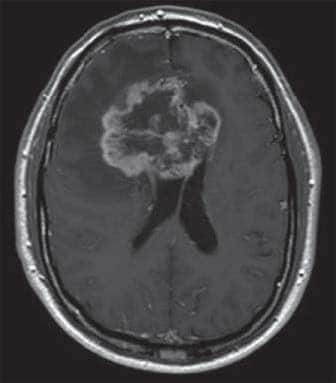

IRM d’un homme de 61 ans présentant des métastases dans l’hémisphère gauche du cerveau secondaire à un cancer du poumon

IRM d’une femme de 88 ans atteinte d’un méningiome de la fosse cérébrale postérieure

IRM d’un homme de 64 ans atteint d’un glioblastome